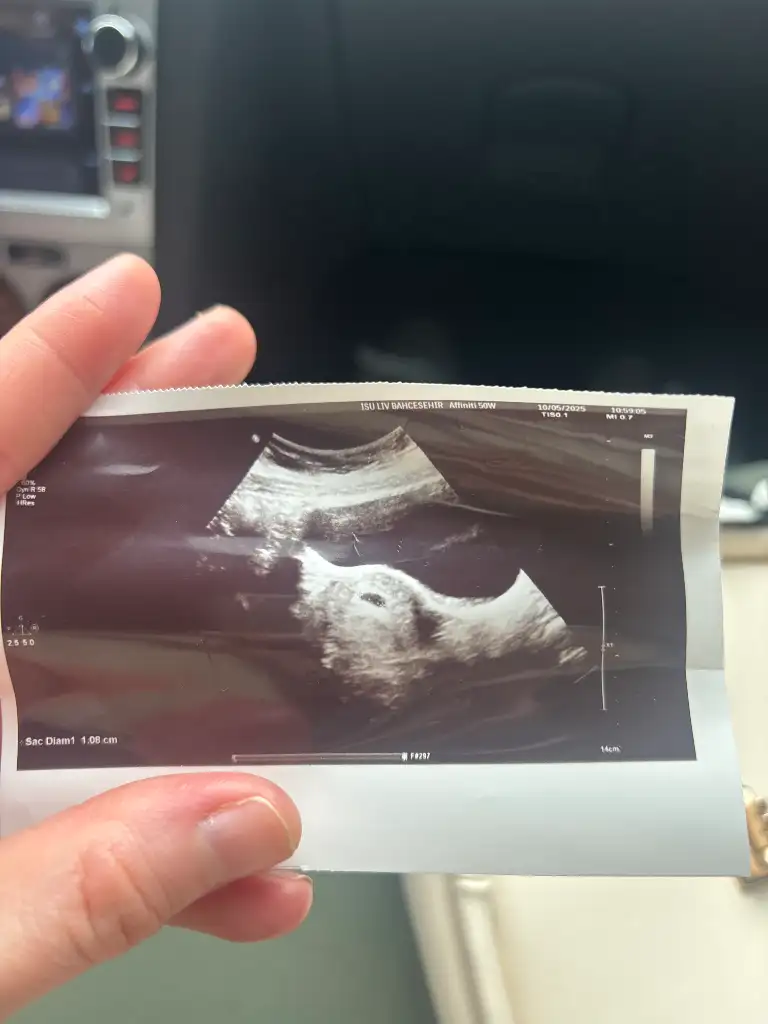

ErkekBanada bakar mısınız? 6+3 vajinal ultrason

Erkeksizce cinsiyeti nedir kızlar